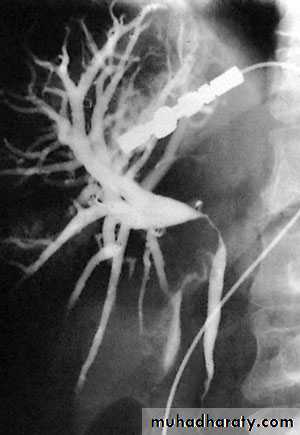

51NORMAL ERCP

Al-Madena copy